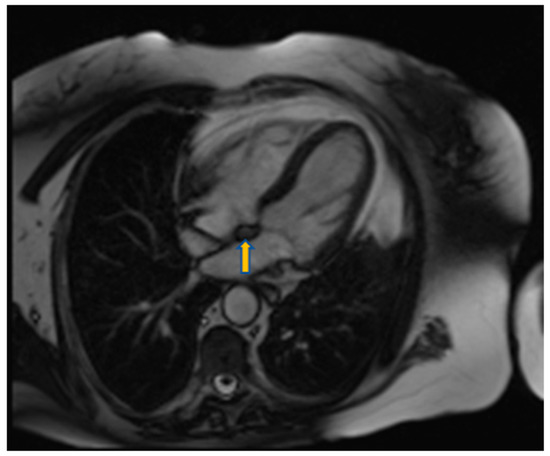

3.4. Cardiac Magnetic Resonance

- Apical and hypertrophic cardiomyopathy may mimic cardiac tumors such as fibromas. In such cases fibromas appear hypointense in T2 weighted images while hypertrophic cardiomyopathy hyperintense. Moreover, CMR tagging can highlight the contractile nature of hypertrophic cardiomyopathy [53,54]. High T1 and low T2 weighted signal intensity is indicative of metastatic malignant melanoma.

- High T1 signal intensity is also seen in lipomas. These masses and other lipomatoses can be recognized with fat suppression techniques (Figure 11).